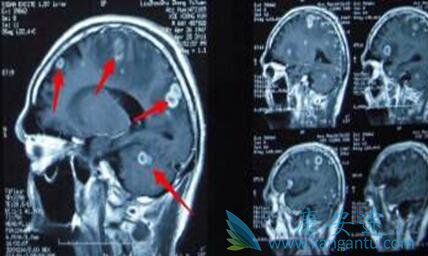

• 常见的肺癌脑转移症状有哪些?

常见的肺癌脑转移症状有哪些?

脑转移 瘤系指原发于身体其他部位的肿瘤细胞转入颅内,其发病率占颅内肿瘤的3.5%-10%,目前以肺癌脑转移最多见。非小细胞肺癌在作出诊断时约有20%的患者已有脑转移,而非小细胞肺癌患者在病程中约有30%左右发生脑转移,其中以大细胞未分化癌和腺癌较多 ...